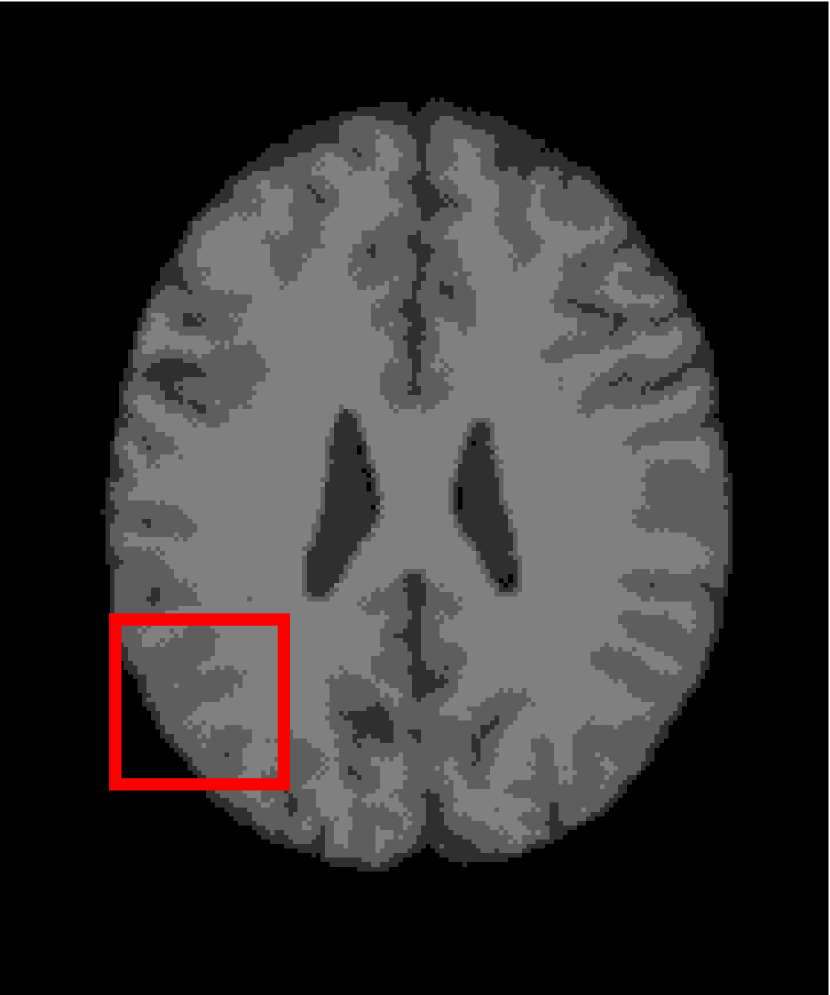

In the second experiments, we segment two medical images coming from a simulated brain database (BrianWeb): http://www.bic.mni.mcgill.ca/brainweb/. The two images are generated by T1 modality with slice thickness of 1mm resolution, 9% noise and 20% intensity non-uniformity. Here, the two images are represented two slices in the axial plane with the sequence of 100 and 110. Moreover, there are golden standard segmentations in the dataset. We set the numbers of clusters to 4. The visual comparisons are illustrated in Figs. 6 and 7.

Figure 6: Segmentation results for the first medical image. From (a) to (l): ground truth, noisy image and results of FCM_S1, FCM_S2, FGFCM, FLICM, KWFLICM, ARKFCM, FRFCM, WFCM, DSFCM_N, and LRFCM.

By focusing on the marked red square in Figs. 6 and 7, we easily find that FCM_S1, FCM_S2, FGFCM and ARKFCM are sensitive to noise. FLICM and KWFLICM are vulnerable to severe intensity inhomogeneity. FRFCM brings overly smooth results due to the use of gray level histograms. WFCM and DSFCM_N cause several contours to change. However, LRFCM acquires clear contours and suppresses noise adequately. Moreover, we find that the segmentation result of LRFCM is closer to ground truth.